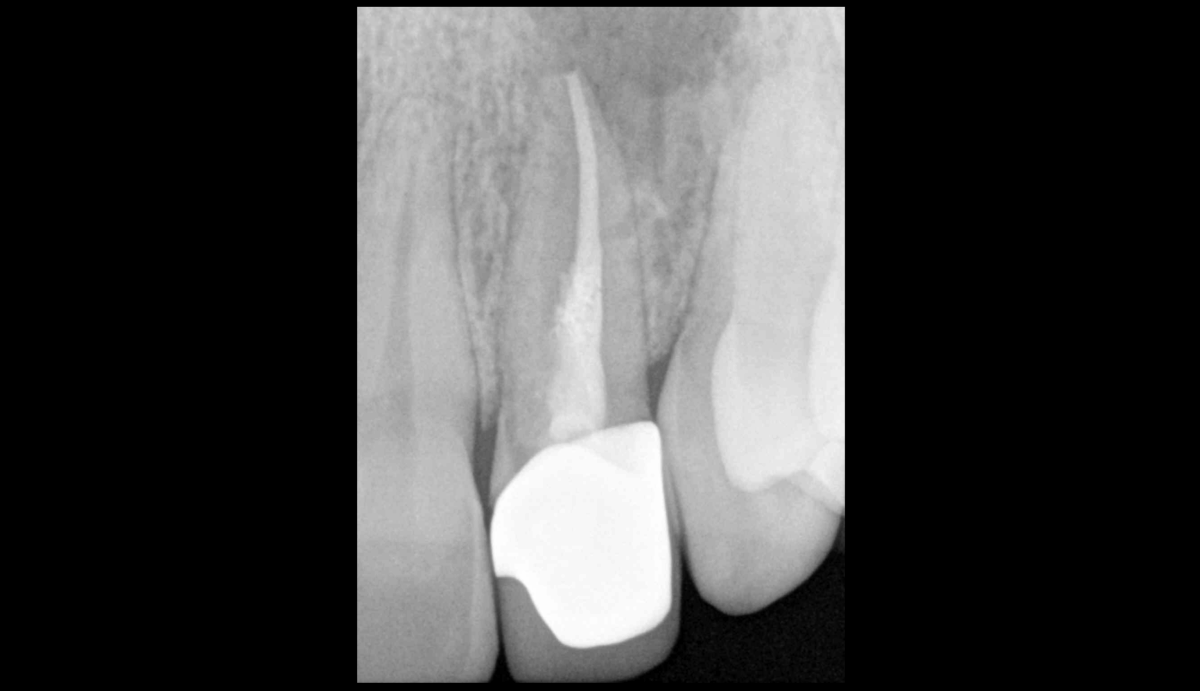

❓ Quel facteur a le plus d’importance dans le traitement/retraitement des canaux : ce que l’on retire ? Ou bien ce que l’on met en place ? 🤔